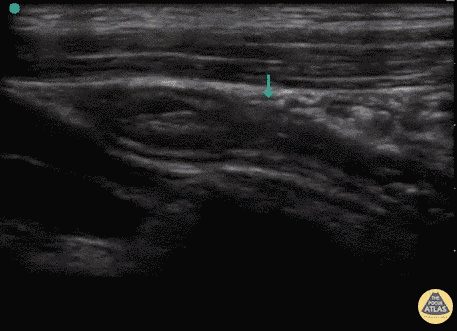

Bowel-GI - Normal Appendix (Longitudinal)

13 y/o F with several days of suprapubic pain, dysuria, nausea, vomiting, tender to palpation in the suprapubic and RLQ area. This study was eventually repeated and confirmed as normal. The appendix was visualized on both longitudinal and transverse views as a blind-ended structure overlying the iliac vessels, a typical location for the appendix. In this view the slightly dilated blind end can be seen to the right of the screen as it tapers off to the left side of the screen. The pulsating iliac vessels can be seen below. This study was eventually repeated and confirmed as normal. Dr. Sathya Subramaniam, Pediatric EM Fellow - Kings County/SUNY Downstate